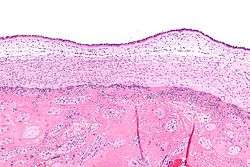

Micrograph showing chorioamnionitis. The clusters of blue dots are inflammatory cells (neutrophils, eosinophils and lymphocytes). H&E stain. | |

Chorioamnionitis can be diagnosed from a histologic examination of the fetal membranes.

Infiltration of the chorionic plate by neutrophils is diagnostic of (mild) chorioamnionitis. More severe chorioamnionitis involves subamniotic tissue and may have fetal membrane necrosis and/or abscess formation.

Severe chorioamnionitis may be accompanied by vasculitis of the umbilical blood vessels (due to the fetus' inflammatory cells) and, if very severe, funisitis (inflammation of the umbilical cord's connective tissue).